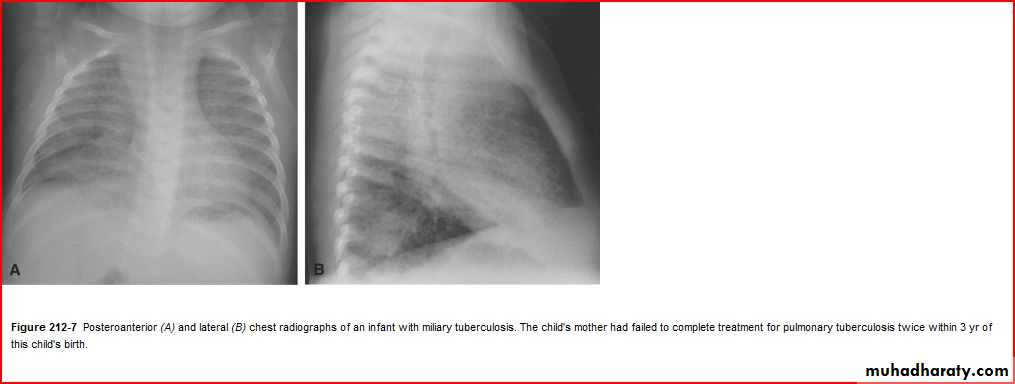

Enlarged hilar lymph nodes + non hemogenous opacity of middle and lower lobe

TBPleural effusion meniscal sign